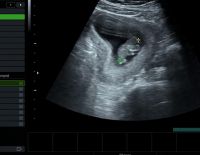

• Siêu âm

Siêu âm 2D là hình thức siêu âm dành cho các mẹ bầu ở những tuần đầu của thai kỳ. Đây là phương pháp siêu âm cũ nhưng vẫn được áp dụng nhiều hiện nay. Khi siêu âm 2D các mẹ bầu vẫn nắm được...

Tác dụng của siêu âm đầu dò âm đạo và những điều cần biết